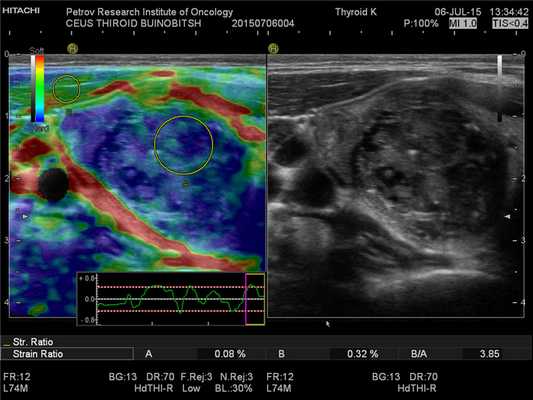

Основной метод диагностики опухолевого процесса в щитовидной и паращитовидных железах — УЗИ. Отсутствие лучевой нагрузки, высокая разрешающая способность, а также доступность оборудования являются очевидными достоинствами эхографии. Особенно справедлив данный тезис, если речь идет об УЗИ с контрастным усилением и применением эластографии. Так называемое, мультипараметрическое УЗИ, то есть вариант исследования с включением в процедуру максимально количества различных методик, является наиболее перспективным вариантом реализации сонографической диагностики, особенно при злокачественной патологии.